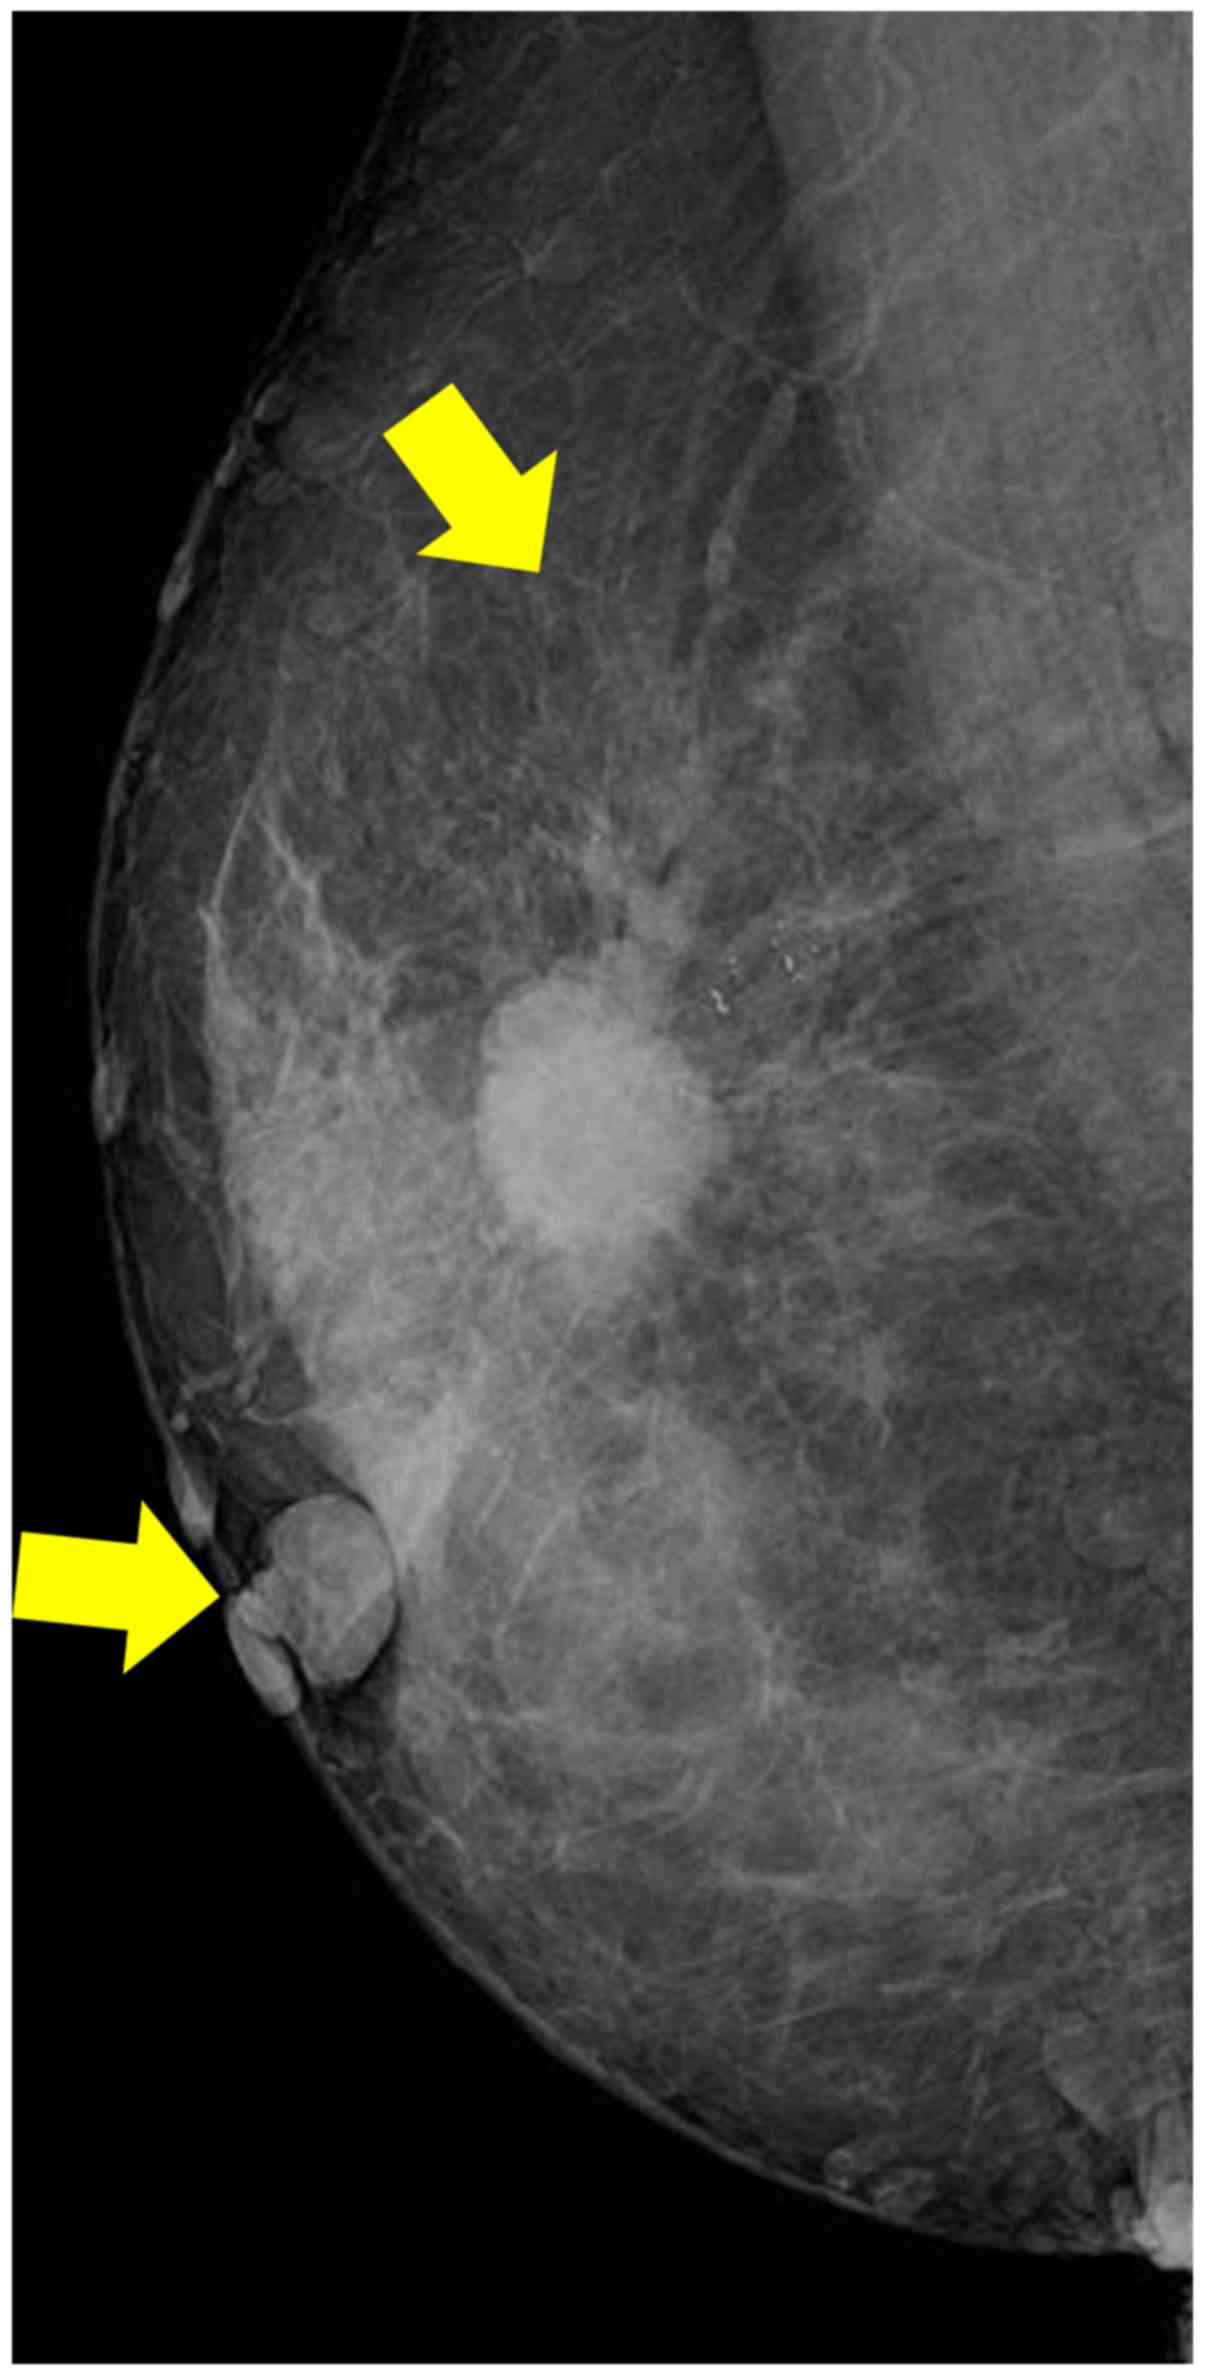

During the present physical examination, a 2-cm tumor was palpated in the upper-outer quadrant of the right breast. The patient presented with classical NF1, indicated by neurofibromas over the trunk (Fig. 1). A high-density microlobulated mass with microcalcifications was observed in the right breast on a mammogram (Fig. 2). The mass was 1.8×1.7 cm in size on ultrasound. Core needle biopsy specimens from the mass revealed invasive ductal carcinoma. Under the clinical diagnosis of T2N0M0 right-sided breast cancer, the patient underwent a modified radical mastectomy and sentinel node biopsy. As the sentinel node was intraoperatively diagnosed as positive for cancer, an axillary dissection was also performed.

Figure 2.

Mammogram of a 67-year old female patient, indicating a high-density microlobulated mass with microcalcifications and neurofibromas (Arrows).